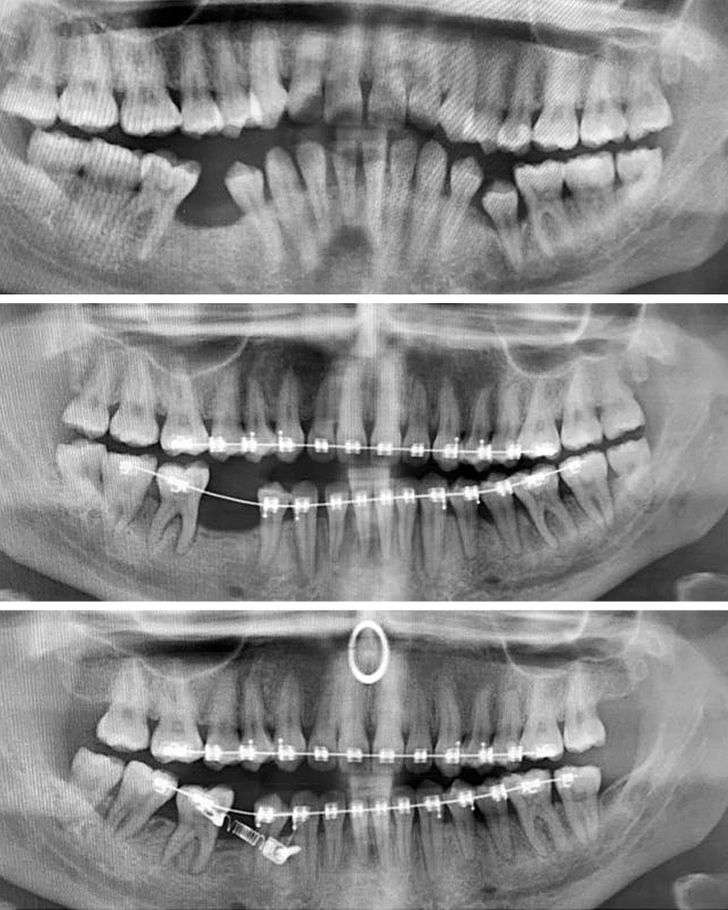

14. Braces may be cumbersome, but they do their job well!

Illustration de l'article : 14 X-ray images that reveal a hidden story

© BoaGirl / Reddit